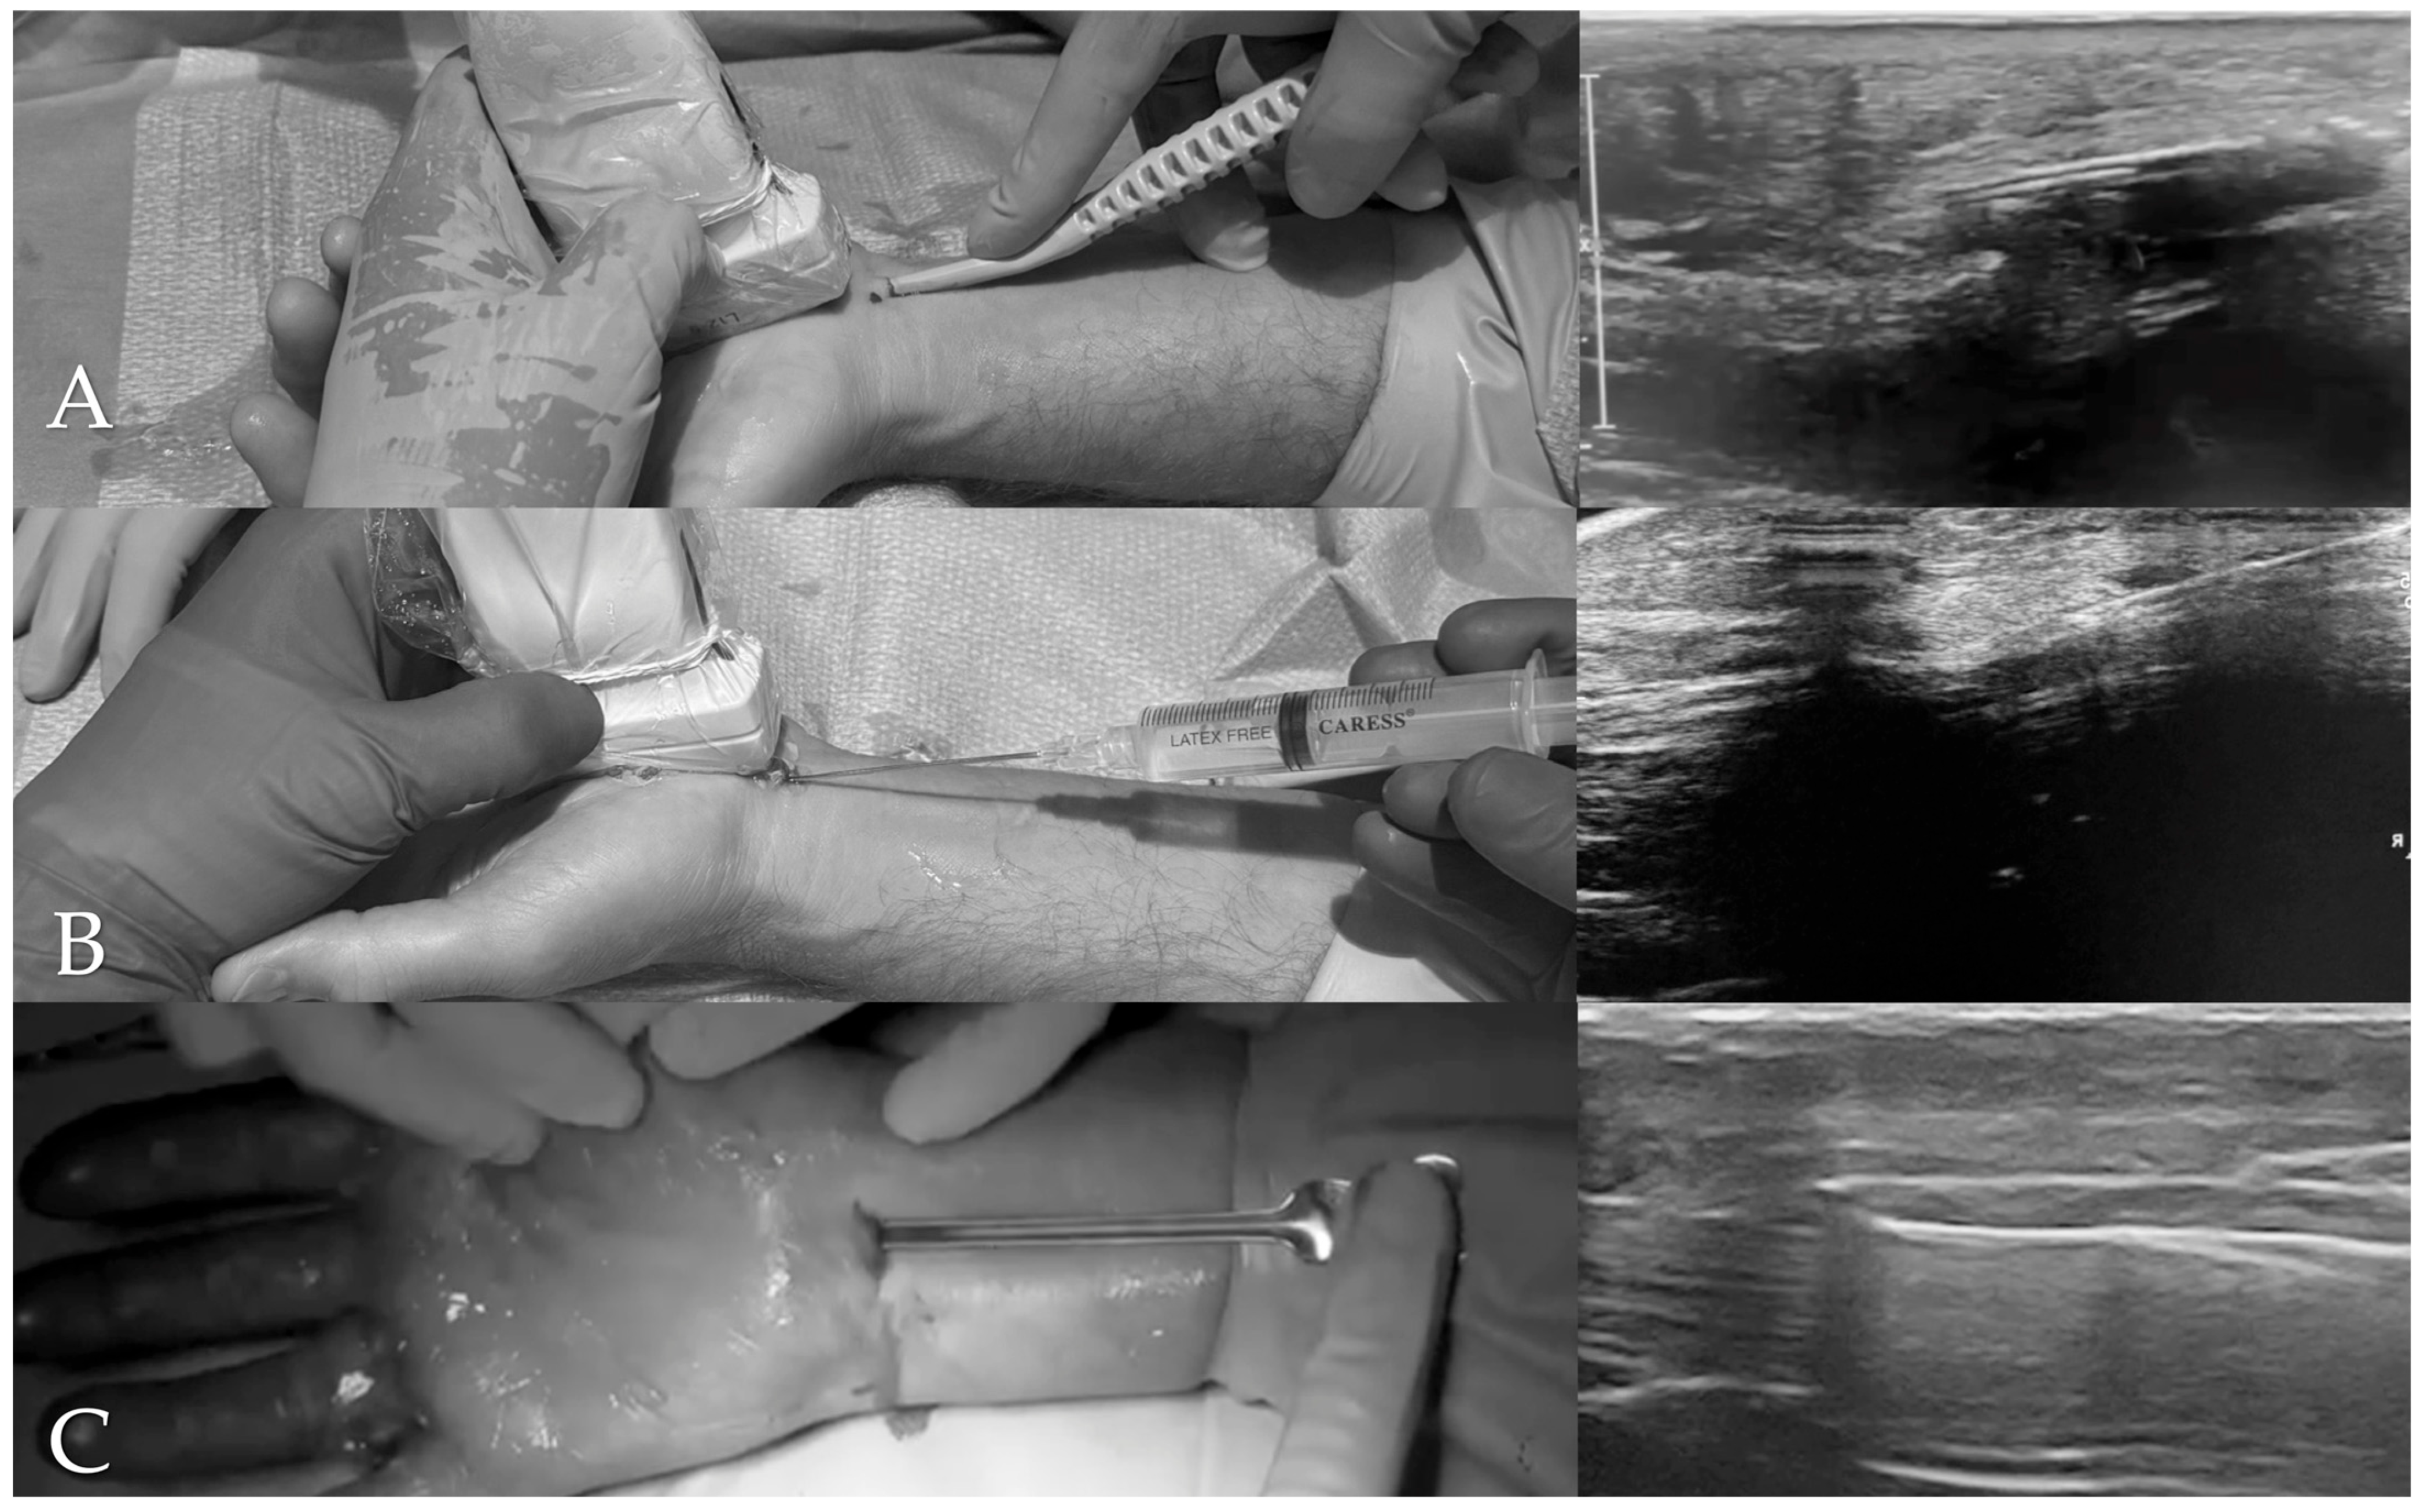

Preoperative pain intensity was assessed using the VAS, with a mean score of 6.37 (SD: 1.56; range: 1–10). The BCTQ showed a mean score of 3.95 (SD: 0.56; range: 2–5) for the BCTQ-SS and 3.59 (SD: 0.91; range: 0–5) for the BCTQ-FS (Figure 2).

At 1 week following surgery, the mean VAS score was 2.20 (SD: 1.70; range: 0–9). The mean BCTQ-SS score was 2.45 (SD: 0.90; range: 1–5), while the BCTQ-FS score averaged 2.32 (SD: 0.93; range: 0–5). Both BCTQ subscales showed significant reductions from baseline (Wilcoxon W = 1094.5, p < 0.0001; and 1851.5, p < 0.0001, respectively).

At 4 weeks postoperatively, the mean VAS score further declined to 1.20 (SD: 1.40; range: 0–7). At 12 weeks, the VAS score continued to improve, reaching a mean of 0.58 (SD: 1.01; range: 0–8). The Friedman test for repeated measures confirmed that these reductions in VAS score were statistically significant (χ2 = 1827.04, p < 0.001).

Figure 2. Progression of clinical scores over time.